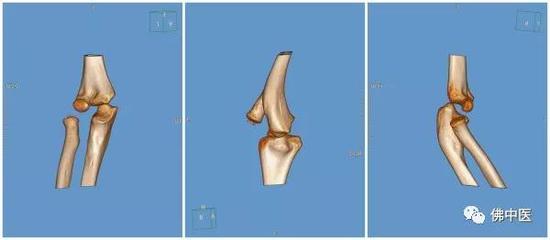

术前,对才巴受伤的肘关节进行CT四维重建